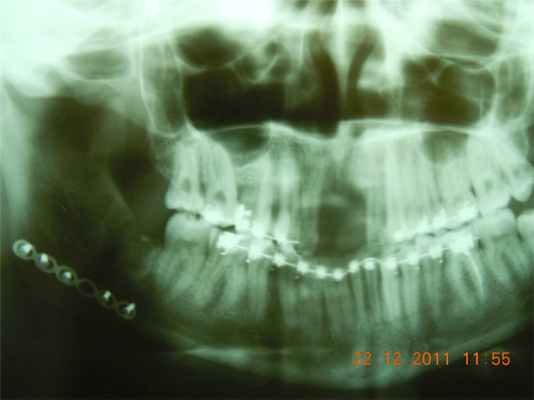

Способ поясняется чертежом. При выполнении операций при множественных переломах костей средней зоны лица пострадавшему вначале производят репозицию отломков скуловой кости крючком Лимберга через разрез-прокол, проведенный в проекции нижнего края тела скуловой кости. Следующим этапом производят прокол-разрез (0,5 см) в области проекции основания скулового отростка лобной кости. Через указанную рану в скуловой отросток лобной кости, а затем через отломки наружного края орбиты в тело скуловой кости вводят спицу Киршнера 1 на глубину 3-4 см. Спицы откусываются на расстоянии 0,5 см от кости. Далее нить в виде проволочной лигатуры 2 из имеющейся раны в области надбровья проводят в подвисочную область, а затем - вдоль внутренней поверхности тела скуловой кости выводят в предварительно выполненную нижнюю рану и, обогнув скуловую кость снизу, проводят подкожно по наружной поверхности скуловой кости, после чего выводят в первоначально выполненную верхнюю рану. Концы проволочной лигатуры подтягивают и фиксируют к концу спицы, выступающему над костью, создавая компрессию в щелях переломов 3. Далее, при необходимости, производят кранио-максиллярный остеосинтез, с которым предлагаемый способ легко комбинируется, так как лигатуры, фиксирующие отломки верхних челюстей, можно зацеплять за концы указанных ранее спиц. Кожные раны зашивают наглухо.

Клинический пример: Пострадавший М., 1971 года рождения, житель г. Аликовского района Чувашской Республики, получил травму 24.09.92 г. на производстве - удар тупым предметом в лицо. С места травмы доставлен в Аликовскую центральную районную больницу в тяжелом состоянии. Через четверо суток, 28.09.92 г. , после стабилизации состояния, проведения интенсивной терапии, временной иммобилизации отломков челюстей и консультации специалистов по линии Санитарной авиации переведен в Отделение сочетанной травмы больницы скорой помощи г. Чебоксары, история болезни N 6934. В результате проведенного обследования больному поставлен диагноз: ОЧМТ. Ушиб головного мозга средней степени тяжести. Субарахноидальное кровоизлияние. Множественный двусторонний перелом костей средней зоны лица: справа по среднему и верхнему уровням, слева по верхнему уровню, сагитали костей носа со смещением. Двусторонний перелом нижней челюсти в подбородочном отделе справа и области тела слева со смещением. 29.09.92 г. пострадавшему под общим обезболиванием произведена операция: закрытый остеосинтез правой скуловой кости по предлагаемому способу, кранио-максиллярный остеосинтез, репозиция костей носа, открытый двусторонний внутриротовой остеосинтез нижней челюсти проволочными швами. 05.10.92 окончательное восстановление прикуса межчелюстным эластическим вытяжением. В послеоперационном периоде получал консервативное лечение, осложнений не было. Через месяц, 28.10.92 г. под местным обезболиванием удалены металлоконструкции, фиксирующие отломки костей лицевого скелета. Патологической подвижности отломков костей лицевого скелета нет. 30.10.92 г. пациент выписан на амбулаторное долечивание у невропатолога по месту жительства, так как лечение переломов костей лицевого скелета закончено в стационаре.